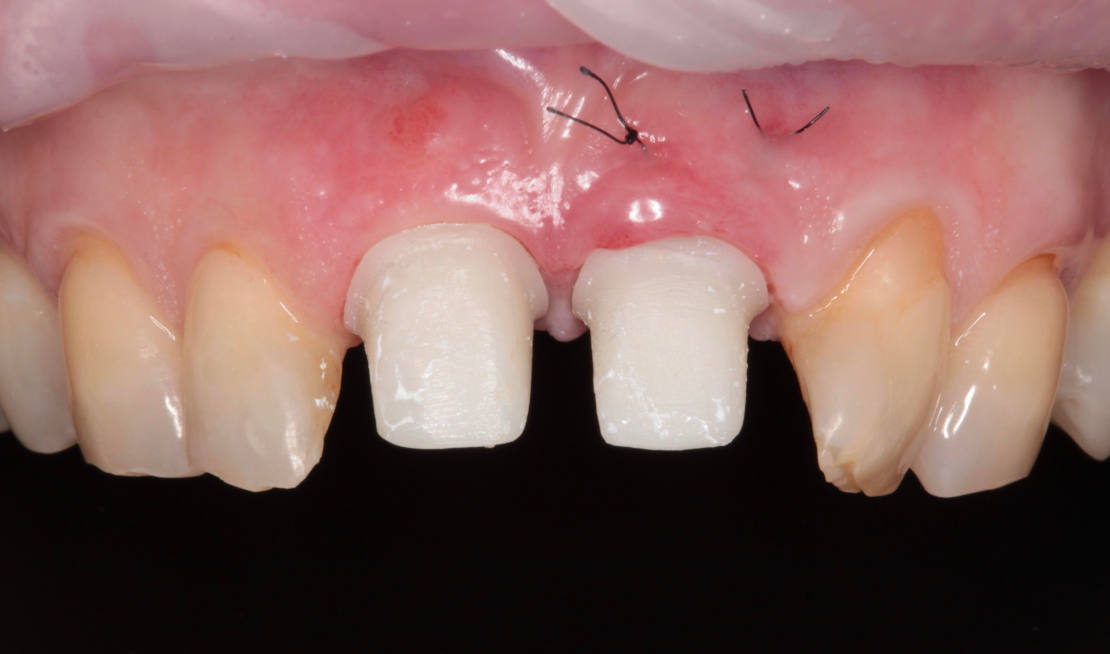

Vďaka týmto postupom bola operácia veľmi rýchla a pacientka odišla z ordinácie plne rehabilitovaná. Minimálne invazívnym spôsobom boli extrahované horné jednotky (obr. 6).

Následne sme použili protokol vŕtania a zavedenia implantátov cez šablónu (obr. 7, 8), na ktorej sme mali orientačné body pre správne napolohovanie implantátov, abutmentov a koruniek (obr. 9–14).

Kontrola po 10 dňoch (obr. 15–19).